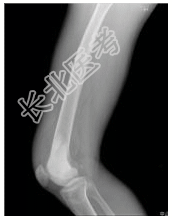

- [材料题] 患者男,21岁,右股骨下端肿痛2月余。查体:右股骨下端压痛,肿胀,可触及软组织肿块。行股骨下段正侧位片检查。

- 简答题1、患者的诊断及依据是什么?

- 简答题2、鉴别诊断是什么?